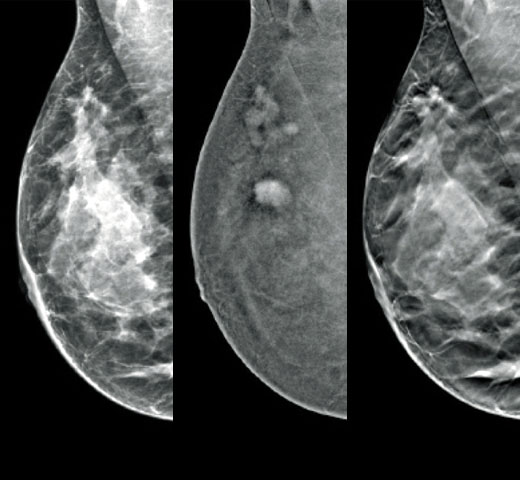

Higher breast density is known to increase a woman’s risk for breast cancer.1 The need for accurate, unbiased analysis is therefore critical. Powered by machine learning, Quantra technology software analyses both 2D™ and tomosynthesis images for distribution and texture of parenchymal tissue. It categorises breasts in four breast composition categories consistent with guidance from the American College of Radiology (ACR) BI-RADS Atlas 5th Edition.2

*Scores are based on ACR BI-RADS categories, in line with the revised guidance by the American College of Radiation (ACR) BI-RADS Atlas 5th Edition. This accounts for pattern and texture, compared with volume, when determining density.

8. Breast composition categories as described in ACR BI-RADS Atlas.